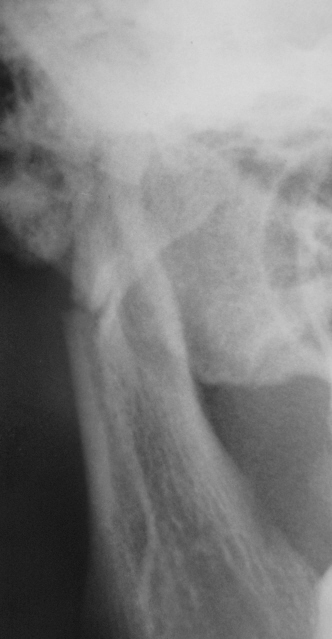

Вот один из них.

Валентин Львович! Результат налицо. Открытый перелом в области 8-го зуба. И на противоположной стороне в области 2-3-го зубов.

Переломы: через лунку 8 с одной стороны, с другой - в обл 3/4.

Замечания: не маркирована сторона, не достаточно косой снимок - наложение сторон. Стоило снять с двух сторон.